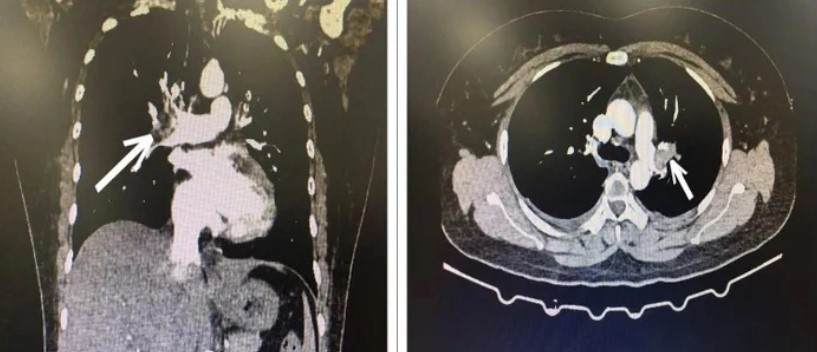

Người phụ nữ bị tắc động mạch phổi do uống 15 viên thuốc tránh thai khẩn cấp/tháng

Vừa qua, khoa Cấp cứu, Bệnh viện Trung ương Quân đội 108 (Hà Nội) tiếp nhận bệnh nhân nữ 34 tuổi, do liên tục lạm dụng thuốc tránh thai khẩn cấp trong suốt 10 năm nên dẫn đến tắc động mạch phổi.